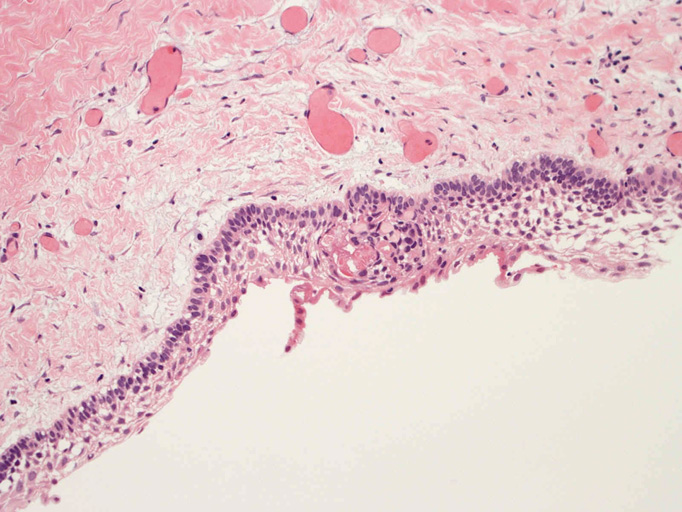

嚢胞性病変の壁を裏装する上皮はspongiosisあるいはintraepithelial edemaと棘細胞への分化を示す。7-15層の上皮で, 基底細胞はpalisadingを呈している。上皮脚は平坦で角化は認められない(Fig.01-Fig.04)。嚢胞壁はわずかにmyxoidな成分を伴うdensな膠原線維性間質からなり, その中に小さな胞巣状の歯原性上皮巣が散在している。核分裂像は認められない(Fig.05, 06)。

病理組織診断:unicystic ameloblastoma, luminal subtype